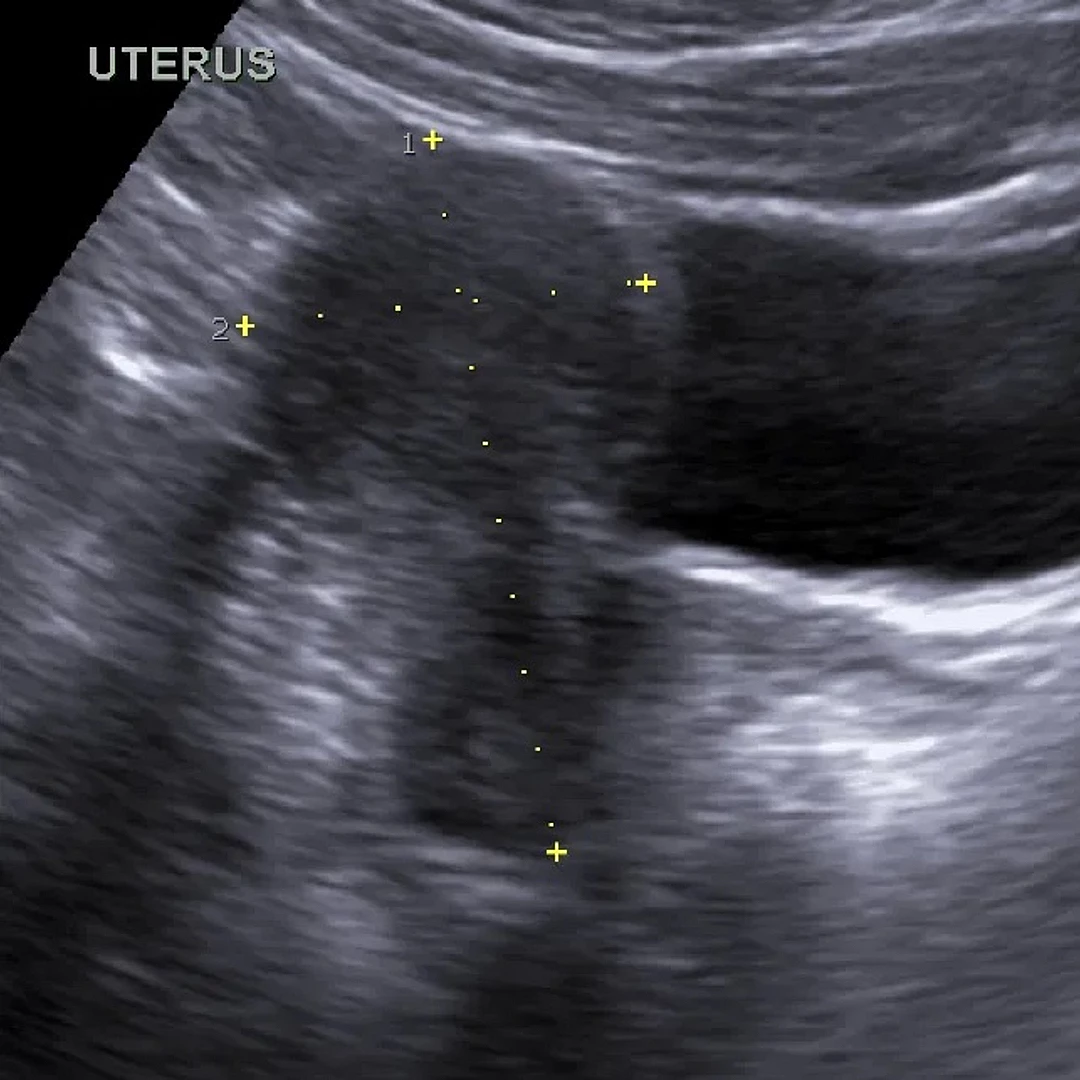

Pelvic Ultrasound

Pelvic Ultrasound offers detailed imaging of the uterus, ovaries, bladder, and other pelvic structures. It’s commonly used to assess reproductive health, pelvic pain, or abnormal bleeding.